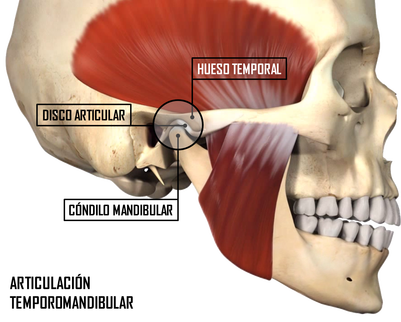

Patología articular

La articulación témporo-mandibular (ATM) es la estructura anatómica encargada de relacionar ambos maxilares. Integrada por el hueso temporal, el cóndilo mandibular y el disco articular, que se interpone entre ambos, guía los movimientos de apertura y cierre bucal, así como los movimientos de lateralidad durante los ciclos de masticación y el habla. Se diferencian en ella dos compartimentos: el superior, entre el hueso temporal y el disco articular, en el que se realiza el movimiento de traslación y un compartimento inferior, entre el disco y el cóndilo mandibular, en el que se realiza el movimiento de rotación. Los diferentes movimientos, así como la limitación de los mismos vendrán determinados por la acción de diversos músculos y ligamentos que participan de la articulación.

Estructura facial y ATM

ATM sana

ATM sana